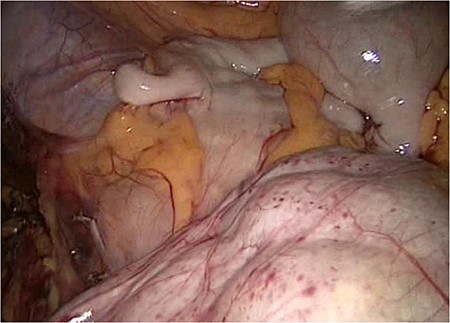

The slim intraperitoneal appendix in the left upper corner with the covered terminal ileum. In the right lower corner, the covered ileum convulse is seen.

Even the terminal ileum seemed to be retroperitoneal. The slim preperitoneal appendix and the terminal retroperitoneal ileum are demonstrated in Fig. 4. The entire ileum was covered by the peritoneum.